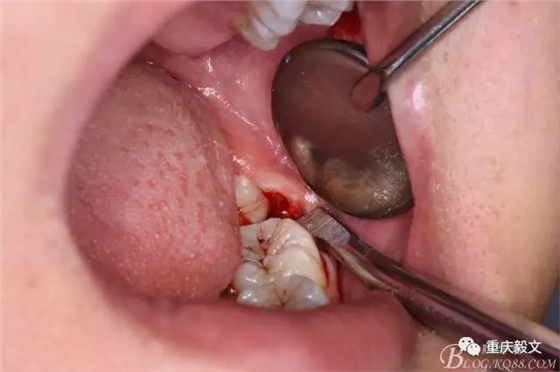

圖7.高速渦輪鉆分牙

圖8.先從頸部橫斷38

圖9.再把38牙冠近遠中縱斷